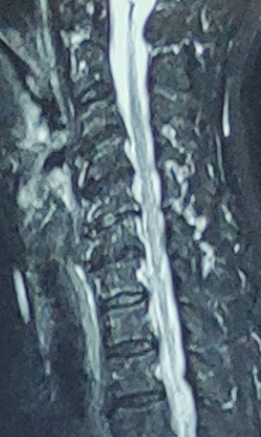

图2 一位80岁老太太颈椎核磁,无神经症状,但每一节都有增生突出表现。